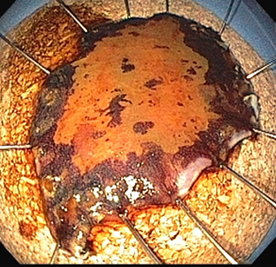

Figura 4 - peça de ressecção com técnica de ESD

Trabalho japonês que analisou os CEC - T1m3 ressecados pela técnica de ESD evidenciou a importância da avaliação da invasão angiolinfática nas peças dissecadas. Entre os pacientes que tiveram invasão angiolinfática identificada no anatomopatológico, 47% evoluíram com metástases no intervalo de cinco anos que se seguiram à ressecção. Já entre os que não tiveram essa invasão vascular observada, a ocorrência de metástases nesse mesmo período foi de apenas 0,7%6.